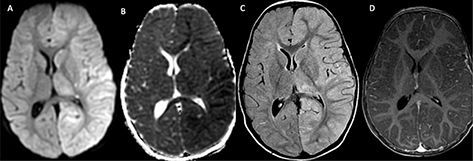

Fig 6

Figure 6. ACTA2 Mutation. Axial ADC (A) demonstrates reduced diffusivity in the periventricular white matter, compatible with acute infarct. 3D Time-of-Flight MRA (B) shows enlargement of the internal carotid arteries (arrowheads) with narrowing of the distal internal carotid arteries (arrow). Follow-up axial T2-weighted image (C) shows evolution of the infarct to cystic encephalomalacia. Case courtesy of Dr. Tamara Feygin, Department of Radiology, Children’s Hospital of Philadelphia.